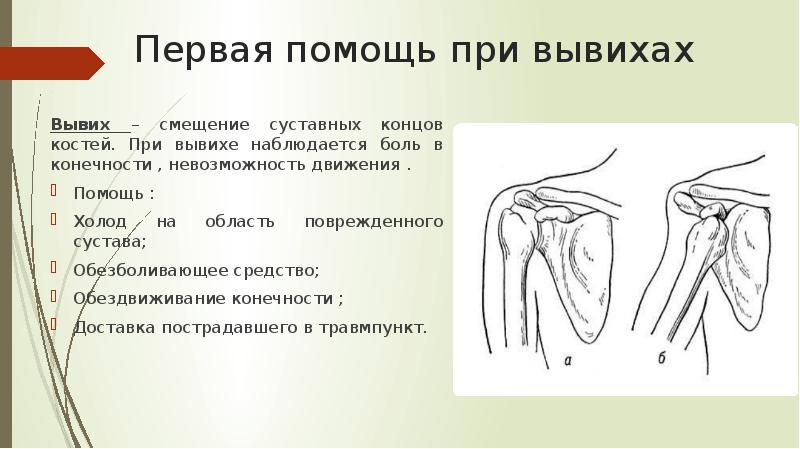

Вывихи и переломы ключицы презентация - 85 фото